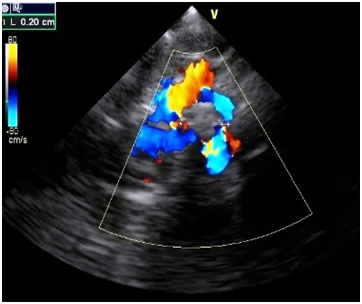

Investigations revealed hemoglobin value of 9g/dL, WBC count 4,000/cumm and platelet count was normal. Liver function test and renal function tests were normal. ECG showed the left ventricular hypertrophy. On chest X-ray there was a normal cardiac silhoutte and a normal lung parenchyma. Transthoracic echocardiography showed parachute-like mitral valve with a severe mitral stenosis (mitral valve size: 0.6 cm2, pressure gradient (Pg: 20 mmHg) causing obstruction to flow Figure 1. Aortic valve was bicuspid with a mild to moderate aortic stenosis (Pg: 40 mm Hg) Figure 2. Severe post-ductal coarctation of aorta with a diastolic tailing was seen on suprasternal view Figure 3. There was a Tiny mid muscular ventricular septal defect with left to right shunt. Small size patent ductus arteriosus with bidirectional shunt mainly left to right was present. Severe tricuspid regurgitation secondary to severe pulmonary hypertension (Right Ventricular systolic pressure = 84mmHg). Pulmonary artery was grossly dilated. There was mild left ventricular hypertrophy with a normal global systolic function and a normal ejection fraction. CT angiography revealed post ductal coarctation of aorta with patent ductus arteriosus with enlarged pulmonary trunk.

Figure 1B Continuous wave doppler studies demonstrated increased peak early (e) and late atrial (a) diastolic flow velocities, peak e-wave velocity is increased, 2.3 m/s.